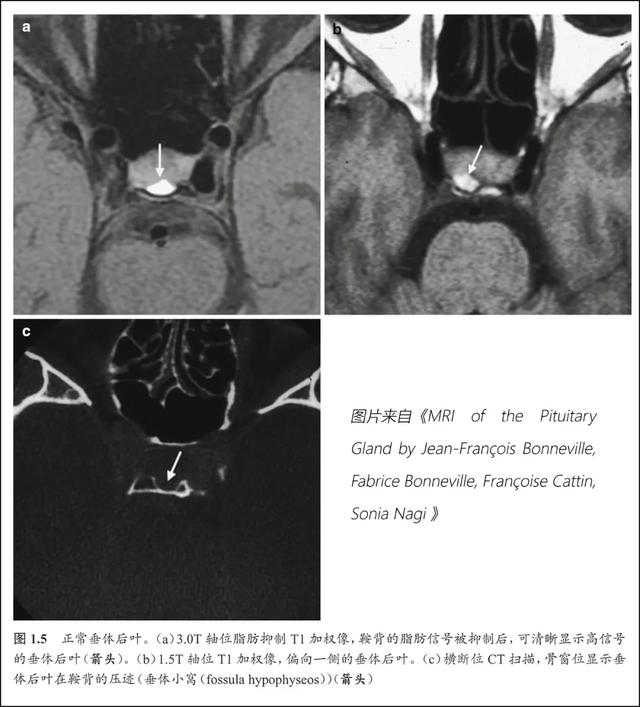

正常垂体的mri表现